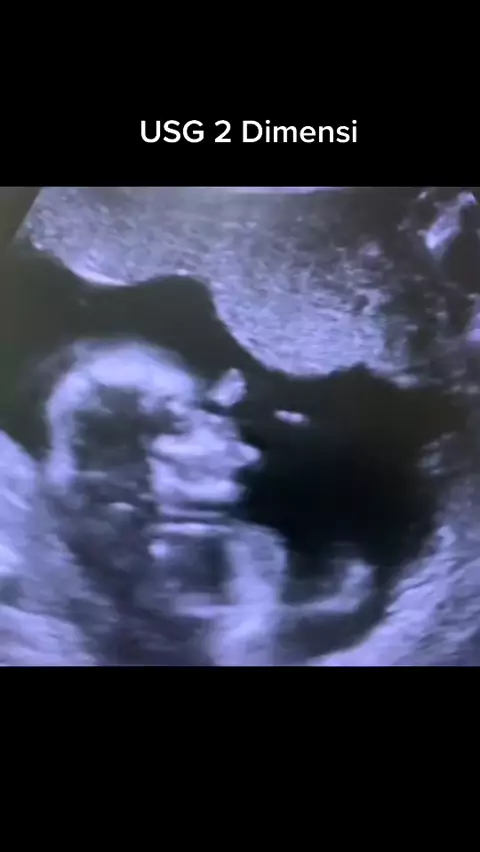

Apa yg bisa kamu lihat? Usg 2 Dimensi #dokterkandunganbatam #spogbatam #usg2dimensi